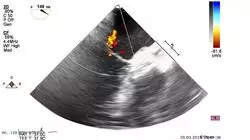

L'Ecografia Clinica è uno strumento essenziale in situazioni di emergenza e cure critiche, in quanto consente di valutare rapidamente gli organi addominali, il cuore, i polmoni e i vasi sanguigni, permettendo ai professionisti di prendere decisioni cliniche basate sui risultati. Questa tecnica è sempre più comune nell'assistenza medica generale, motivo per cui la TECH Università Tecnologica ha sviluppato un completo Tirocinio in Ecografia Clinica in Medicina d’Urgenza e Terapia Intensiva, che include non solo i contenuti più aggiornati nel suo piano di studio, ma anche una metodologia pragmatica unica nel suo genere sul mercato. In questo programma, progettato da specialisti del settore, imparerai a eseguire ed interpretare ecografie degli organi addominali, del cuore, dei polmoni e dei vasi sanguigni. Sarai in grado di identificare i modelli delle malattie comuni e prendere decisioni cliniche basate sui risultati dell'ecografia.

L'ecografia addominale in situazioni di emergenza, l'ecocardiografia in pazienti critici, la valutazione polmonare tramite ecografia in pazienti con insufficienza respiratoria acuta, l'ecografia dei vasi sanguigni in situazioni di trauma o emergenza e i modelli delle malattie comuni nell'ecografia clinica d'emergenza sono alcune delle tematiche che imparerai iscrivendoti a questo completo Tirocinio di TECH. Ci impegniamo a formare professionisti di alto livello in modo che possano migliorare sia il loro reddito che le loro competenze in questo settore sanitario. Per questo ti offriamo il miglior programma disponibile per ottimizzare il tuo curriculum. Garantiamo lezioni di alta qualità potenziate da tecnologia multimedia avanzata e lo sviluppo di casi pratici che rafforzeranno le tue conoscenze. Al termine del tirocinio, sarai in grado di effettuare valutazioni rapide e precise che contribuiranno a salvare vite.